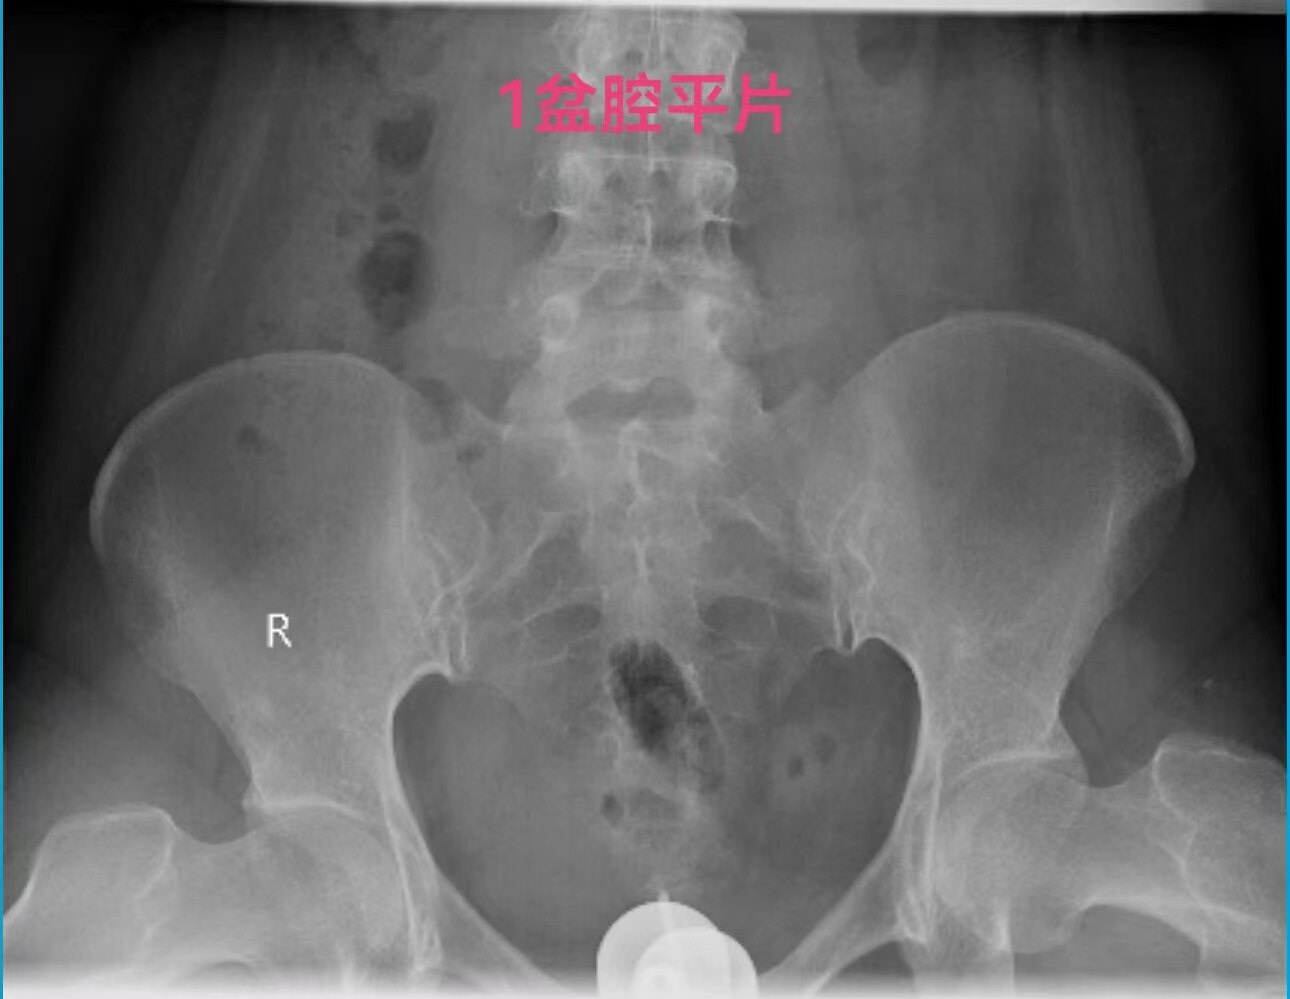

在做子宫输卵管造影检查时:当所用造影剂为碘油,出现静脉和淋巴管逆流时,立即停止造影检查是对的。因为碘油和血液不能相容混合一起,碘油会形成油栓。因此,当碘油进入静脉和淋巴管后会进入下腔静脉,进入右心房,进而进入肺动脉,形成肺栓塞,可危机被检查者生命安全。但是,当所用造影剂为碘水,出现静脉和淋巴管逆流时,可以继续造影检查,直至满足临床诊断后再结束检查。因为碘水和血液可以相容会混合一起,碘水逆流进入静脉和淋巴是安全的。大家好多做过CT增强检查,成年人一般需要用高压注射器要向静脉内快速注入100毫升碘水进行检查,都是安全的。造影注入10毫升左右碘水,即使都进入静脉也没事。这二例,一例碘油造影是一大学附属妇产医院做放射科的,该立即停止造影却没有停止。万幸,逆流进入静脉的碘油少,没有造成严重后果。另外一例碘水造影是一省妇幼保健院放射科做的,不该停止造影检查,反而停止造影检查,未能完成检查,不能给正确诊断。

第一例碘油造影图和报告单